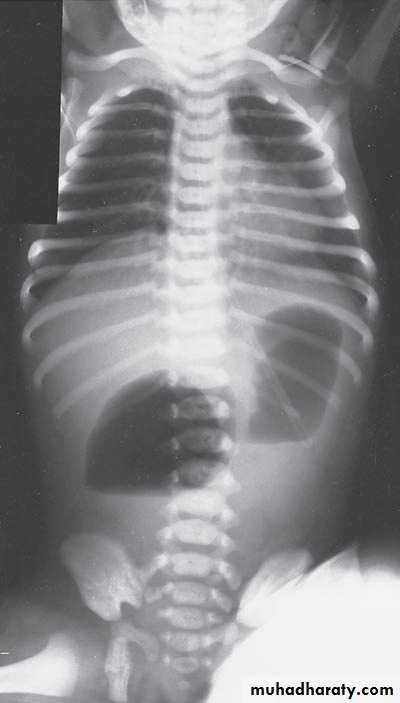

N.E.C